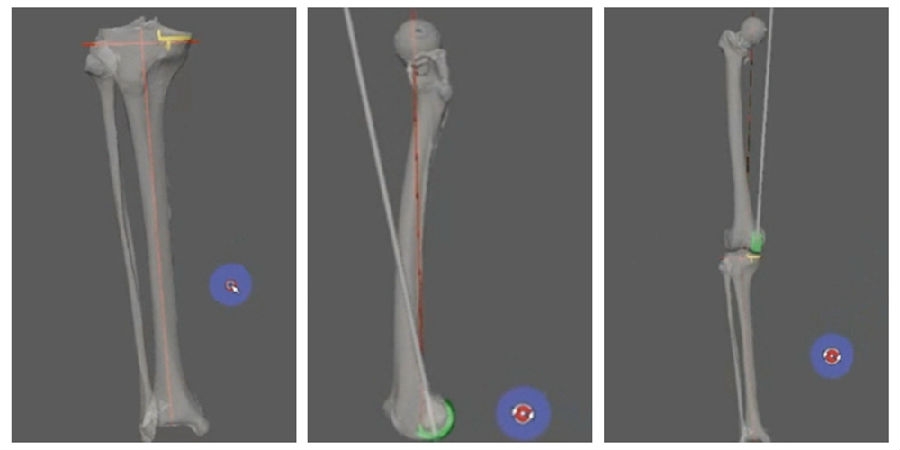

3D打印截骨导板术前规划,要跟工程师细致认真的沟通,三维假体的位置,以及导板相应的贴附区。

术前规划

1、具体操作-术前要求

①基本信息:患者名字首字母缩写、患侧、术式、假体耗材;

②影像采集要求:下肢全长CT或分段CT(包括完整的髋、膝、踝关节,膝上、下15cm,髋下、踝上15cm),全长正位片;

③间距/层厚≤1毫米;

④数据格式:原始DICOM(.dcm);

⑤数据传输需要和销售人员对接;

⑥术者和工程师沟通术前规划。

术前确认方案,包括大小型号,冠状矢状以及轴面上不同位置,如何选择每个人比较合适的假体相关位置。

术前确认方案

同时,笔者团队也在和导板公司进行合作,把用术后CT和术前CT进行匹配,来验证术前规划的偏离度有多少,包括胫骨后倾、冠状面内倾、轴面胫骨假体旋转、股骨在冠状面的角度、股骨在轴面上的旋转角度以及在矢状面上屈伸角度。

符合度验证